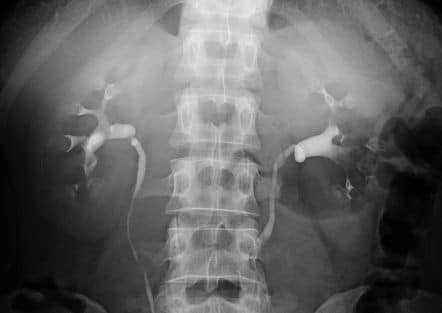

Bệnh lý xốp tủy thận (Medullary Sponge Kidney)

Quy trình kỹ thuật: Nội soi ống mềm tán sỏi niệu quản – thận ngược dòng bằng laser

Nội soi ngược dòng ống mềm tán sỏi thận – niệu quản bằng laser

[Slideshare] Tán sỏi ngoài cơ thể – Điều trị sỏi thận không xâm lấn